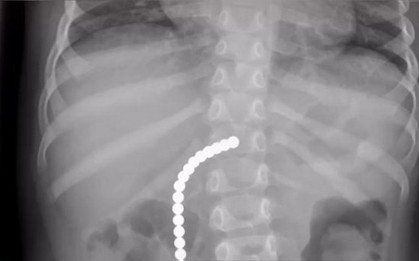

Bé trai 8 tuổi tử vong thương tâm vì “đu trend” TikTok, kết quả khám nghiệm sau khi qua đời khiến bố mẹ bàng hoàng

Thử thách TikTok có vẻ đơn giản đã cướp đi mạng sống của cậu bé 8 tuổi người Anh.